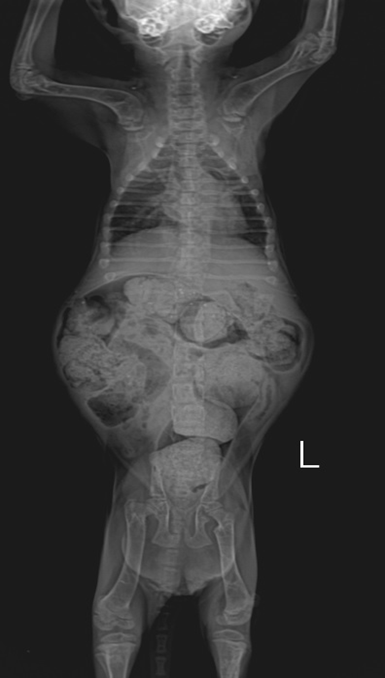

두 번째로 유의해야 할 행동은 고양이가 좋아한다고 해서 '완전 식이'(Complete diet), 주식이 아닌 간식만을 지속적으로 급여하는 겁니다. 실제로 어린 고양이에게 간식 닭고기 캔만을 먹인 아기 고양이의 방사선 사진을 보면 '영양성 부갑상선 기능 항진증'이 유발되어서 아기 고양이의 다리가 부러지고 악성 변비가 유발된 것이 확인됩니다.

이처럼 잘못된 식이로 심각한 건강 문제가 생기는 사례를 임상 현장에서 곧잘 만나곤 합니다. 아깽이는 체내 비축분이 적고 체구가 작기 때문에 급여에 의한 건강 상태가 단기간에 심각한 상태로 이어질 수 있으므로 꼭 주식을 먹여야 합니다. 만약 아기 고양이가 간식 캔만 먹으면, 주식 사료를 조금씩 섞어서 먹을 수 있도록 점진적으로 교육해 주세요.